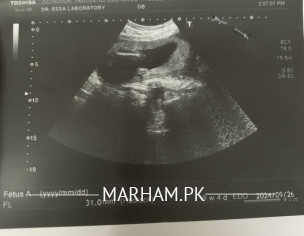

Salam, I am just about to complete my 20 weeks pregnancy journey, and my doctor asked me to do an anomaly scan. The ultrasound technician told me that I’m having a baby boy, but I’ve some doubts because I’ve heard that women with anterior placenta are mostly pregnant with baby girls. Can somebody please tell me by taking a look at my ultrasound pictures that am I having a baby boy or a baby girl? And is everything normal in my anomaly scan? Thank you in advance!

no dear placenta localisation is other thing. and anomaly is other

it's a myth , placement of placenta has nothing to do with gender.. you pics are not uploading??